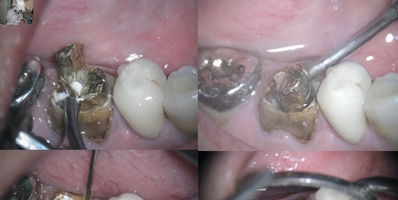

Vários são os casos em que dentes tratados endodonticamente necessitam de restauração com pinos intra-radiculares. E por necessidade de retratamento é necessário a sua remoção.

Existem vários recursos utilizados para a remoção dos retentores intra-radiculares: ultrassom, brocas e saca pinos.

Os meios mais seguros são através de sistema  ultrassônico, por não exigirem força mecânica contra as paredes da raiz do dente, evitando o efeito de alavanca, e por conseguinte evitando fraturas.

Desde 1995  venho realizando a remoção de pinos com o Sistema Integrado e Simultâneo de Ultrassom. Que significa o uso de dois aparelhos trabalhando ao mesmo tempo em sentidos opostos. Para esta manobra utilizo dois aparelhos ENAC OE5O – Osada com ponts STO9.

O sistema de ultrassom transforma a energia elétrica em energia mecânica. Quando age em sentidos opostos é criada uma zona de justaposição onde a soma das ondas mecânicas potencializa a ação ultrassônica quebrando o cimento com mais facilidade. Portanto deslocando o pino da sua posição original.